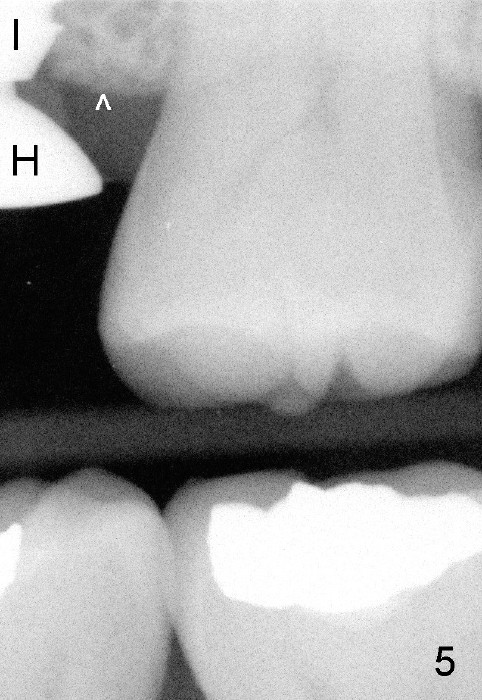

A 45-year-old man has lost the tooth #14 for a while (Fig.1); bone height is 5.4 mm. An extra wide and short implant is planned. Torus palatinus is large, suggesting that bone density should be high. A 6 mm tissue punch is chosen, but it is placed more palatal. If it were placed in the middle of the ridge, there would be no buccal keratinized gingiva (incision may avoid this issue). Additionally, the buccal portion of punch is made incomplete so that there is pedicle on the buccal side when the flap is raised (Fig.4,8: F). It is expected that the excess portion of keratinized tissue will form thick gingiva buccally. Osteotomy proves that bone is dense (Fig.2 (4.5x11 mm tap). Typical sinus lift is finished with placement of 6.4x6 mm (extra wide) bone-level implant (Fig.3, >55 Ncm). Following further torque, Fig.4 shows that the implant (I) is sub-gingival (<). Bitewings are taken to confirm that the implant plateau is at the crestal level (Fig.5,6 ^). PA shows sinus lift (Fig.7 *). The lingual aspect of the implant and healing abutment (H) is further bone grafted and covered by collagen dressing (Fig.8 *). The wound is protected with perio dressing. When the latter dislodges 7 days postop, the collagen dressing and bone graft are lost as well (Fig.10), while the buccal flap remains vital (Fig.9). The lingual exposed plateau should be able to heal normal. The collagen dressing should have been fixed in place by suture or as simple as a dental floss. There is mild nasal hemorrhage 1-2 days postop, possibly related to sinus membrane perforation and inability of Collagen Dressing to cover the perforation and contain the bone graft. When the patient returns for #9 implant placement in 3 weeks postop, the buccal flap reduces in size (Fig.11 *), while the palatal wound has healed with minimal exposure of the implant (Fig.12). Sinus graft remains in place 3 months postop (Fig.13); the buccal flap appears to have incorporated into a part of the gingiva (Fig.14). The bone density of the sinus lift appears to increase 10 days later when an abutment is placed (Fig.15 *). Although oral hygiene is pristine, there is apparent crestal bone resorption 12 months (Fig.16) and 20 months (Fig.17) post cementation, probably due to unfavorable crown/implant ratio and bruxism as well as pre-implantation bone loss (Fig.18,19). In contrast, an immediate implant in the same patient avoids pre- or post-implantation bone loss. In fact both the soft (Fig.20) and hard (Fig.21) tissues remain healthy 2 years 8 months post cementation. The sinus lift remains 3 years 8 months post cementation (Fig.22), while the crestal bone loss persists. The patients keeps complains of food impaction distal associated with bad smell 4 years 1 month post cementation. In fact the distal proximal contact is within normal limit. The bad smell is probably due to crestal bone loss (Fig.23 (pan), 24 (CT) *) and periimplantitis. Bone graft, PRF and Cytoplast membrane will be needed and fixed in place with long healing screw. When the patient returns for crown redo, he also reveals floss related gingival hemorrhage. There is pain associated with palatal sulcus probing with light gingiva erythema. Review of CT coronal section shows possible palatal (Fig.25 P) bone loss (*).